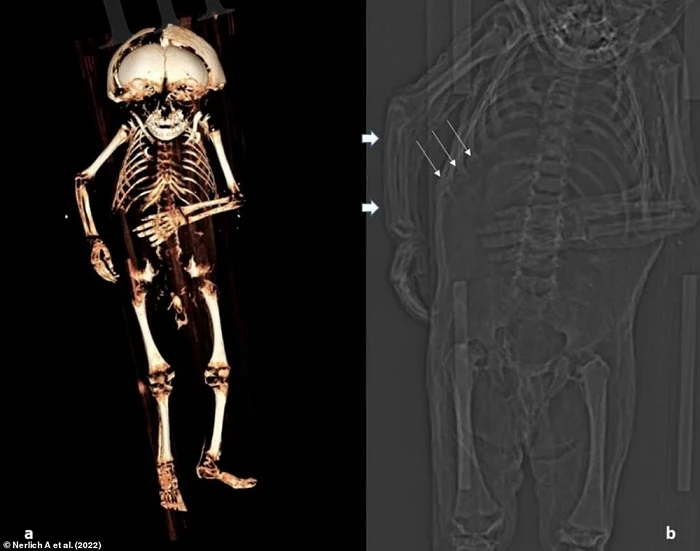

Các nhà nghiên cứu từ Phòng thí nghiệm Munich-Bogenhausen của Đức xác định rằng, cậu bé có khả năng mang tên là Reichard Wilhelm và đã chết vào năm 1625 hoặc 1626, cách đây khoảng 4 thế kỷ. Cơ thể của cậu bé được bảo quản khá tốt bằng phương pháp ướp xác. Điều này cho phép các nhà nghiên cứu có thể phân tích mô mềm của xác ướp bằng cách sử dụng máy quét CT.

Các nhà khoa học cũng đã nghiên cứu răng cũng như đo xương của đứa trẻ. Kết quả cho thấy em bé này từ 12 - 18 tháng tuổi khi qua đời. Cậu bé có mái tóc đen và thừa cân so với tuổi của mình, cho thấy cậu đã được ăn uống và chăm sóc đầy đủ.

Tuy nhiên, kết quả chụp CT thể hiện xương sườn của cậu bị biến dạng, dấu hiệu của căn bệnh chuyển hóa xương (Metabolic Bone Disease - MBD) thường được thấy trong các trường hợp mắc bệnh còi xương nghiêm trọng. Hình ảnh chụp cắt lớp cũng cho thấy tình trạng đặc trưng của bệnh viêm phổi.